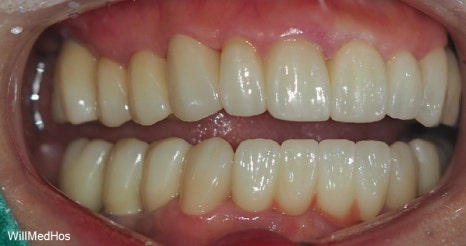

이렇게 전치부 앞쪽 치아들은 심미적인 부분과 기능적인 부분 두가지가 충족이 되어야 하기에

PMMA (수정 할 수 있는 최종 전 보철) 사용해보시면서 환자분의 주변 치아 색상과도 어우러 질 수 있도록

원하시는 모양이나 피드백들을 받아 최종적으로 제작 하게 됩니다.

최종 치료 완료된 구강 모습입니다. 앞전의 구강 사진과 비교해보시면 자연스러운 치아의 모습이 완성된것을 확인 할수 있습니다.